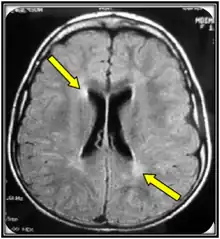

Diagnosis

Clinical examination and MRI are often the first steps in an MLD diagnosis. MRI can be indicative of MLD but is not adequate as a confirming test. An ARSA-A enzyme level blood test with a confirming urinary sulfatide test is the best biochemical test for MLD. The confirming urinary sulfatide is important to distinguish between MLD and pseudo-MLD blood results. Genomic sequencing may also confirm MLD, however, there are likely more mutations than the over 200 already known to cause MLD that are not yet ascribed to MLD that cause MLD so in those cases a biochemical test is still warranted.